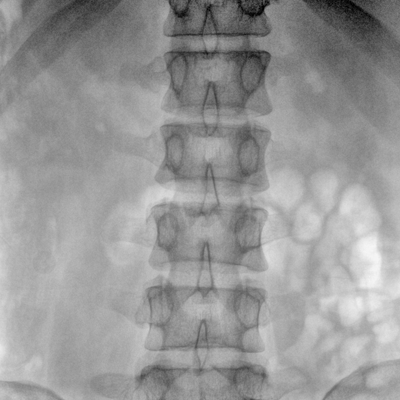

臨床適用科室:骨科、普通外科、矯形外科、創(chuàng)傷外科、泌尿外科、脊柱外科、疼痛外科、消化科、婦科等科室。

大尺寸動態(tài)平板探測器,高DQE、低噪聲、圖像清晰。采用多分辨率圖像增強(qiáng)處理技術(shù),不同部位不同圖像處理算法,滿足客戶多樣化的需求。